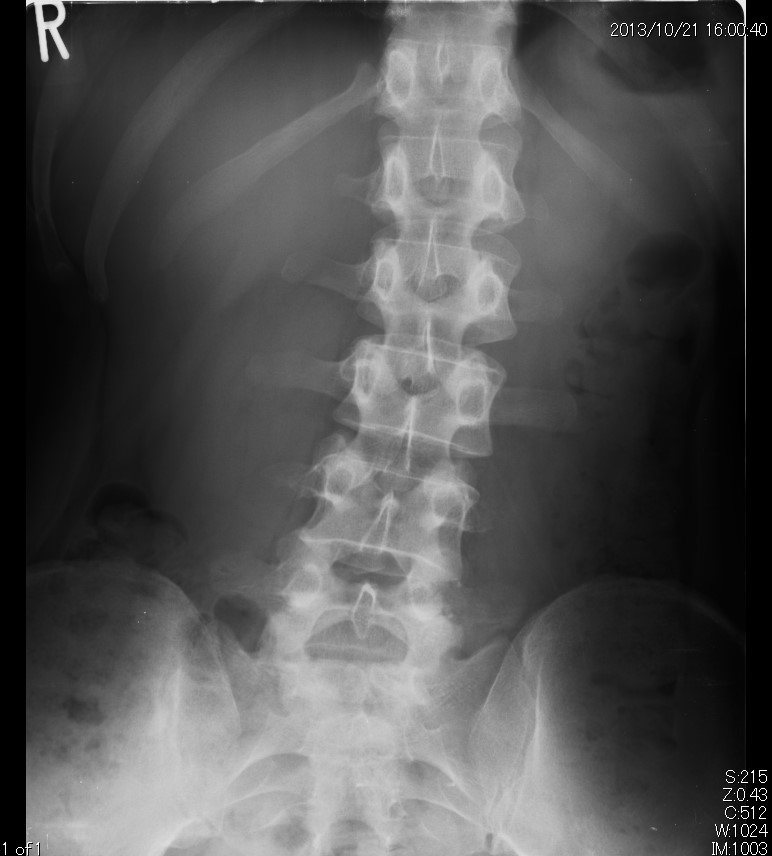

病院で検査してもらったところ「L4とL5椎間板髄核は脱出がみられ、脊柱管狭窄を呈しています」とのこと。